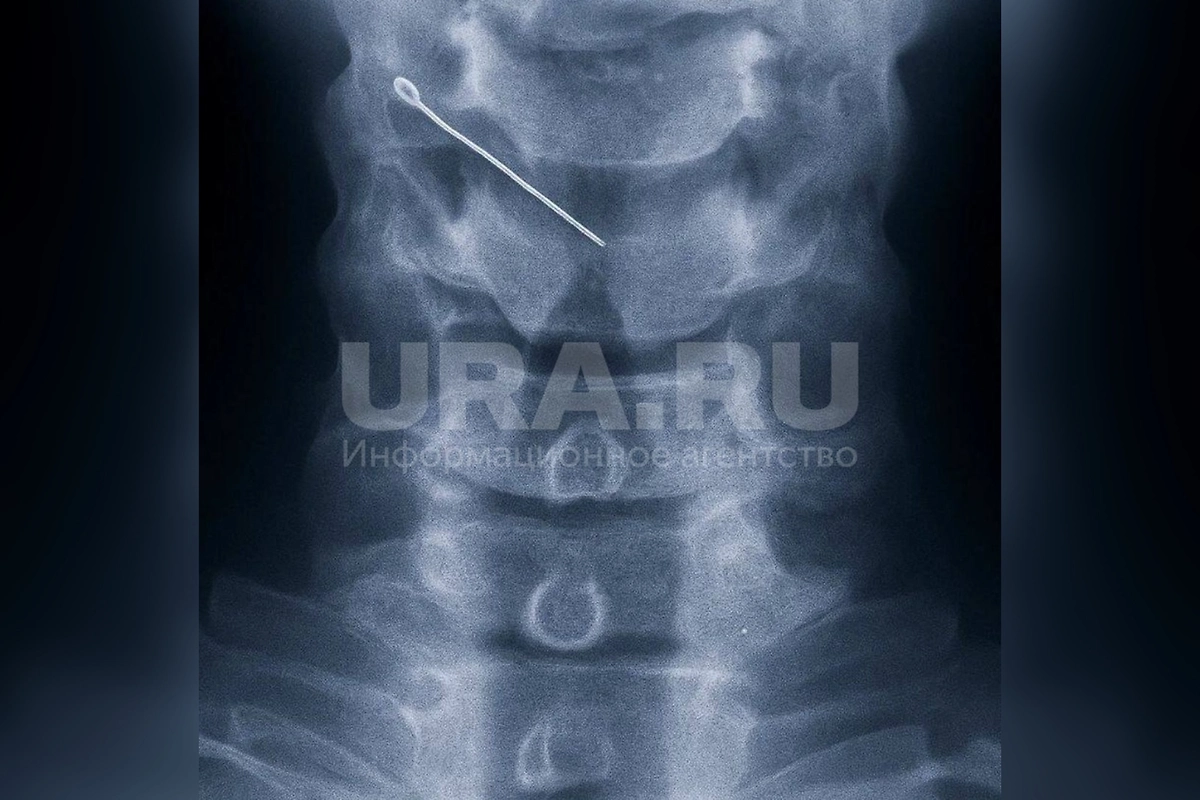

Рентген. Фото © Telegram / URA.RU

«В больницу пациентка обратилась сразу, с жалобами на сильную боль при глотании. На рентгене уточнили местоположение иглы, извлекать пришлось под наркозом, через рот», — рассказал врач.